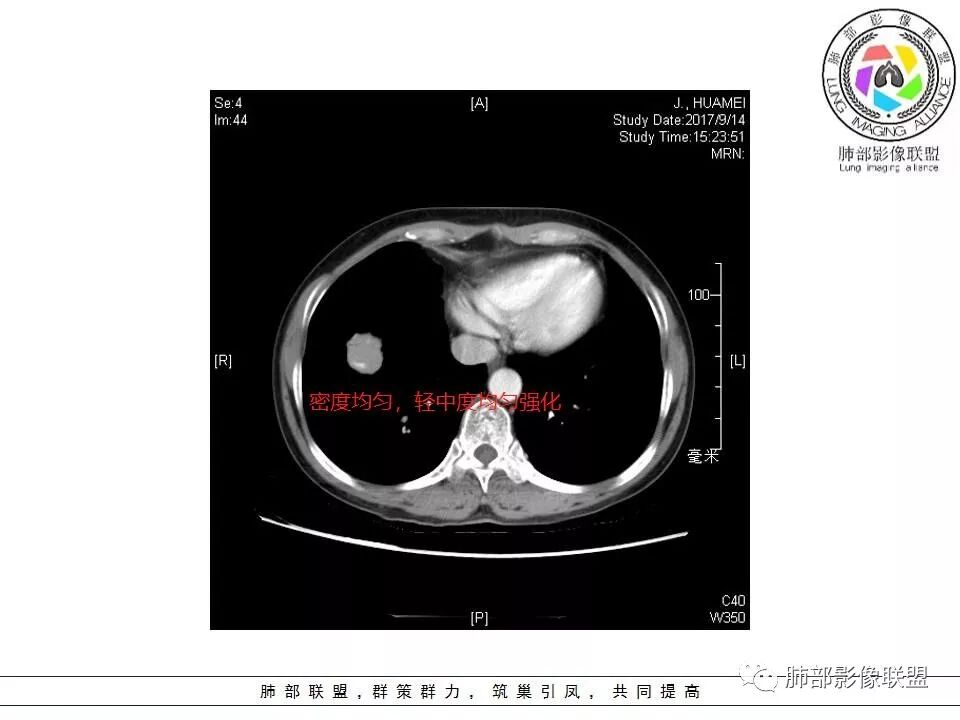

晨读:右下肺前基底段支气管亚段分叉处占位,密度均匀、中度均匀强化,结节近边缘有支气管、血管穿行,结节边缘较光滑、有细短毛刺、无分叶,结节周围无卫星灶。考虑:PSP,鉴别:小细胞肺癌、不典型错钩瘤

轻度分叶,支气管穿行,轻中度强化,血管漂浮,考虑MALT

右肺下叶前基底段结节 边缘磨玻璃密度较清 内部支气管扩张,轻中度强化 穿行血管形态自然,支持淋巴瘤。

晨读,右肺下叶前基底段实性结节,边缘膨隆,可见多发浅分叶,结节内密度均匀,增强后呈轻度均匀强化,血管穿行走形自然,首先考虑恶性肿瘤,内有支气管穿行,淋巴瘤可能大,腺癌待排。

边缘彭隆,还是考虑肿瘤,支气管通入,肺内原发,支气管自然穿行稍扩张,血管比较自然同行,漂浮征,增强后整个比较均匀无明显坏死,淋巴瘤首选。恶性应该没有问题,建议穿刺。

内部支气管走形非常自然,达远端稍扩张;内部血管穿行也非常自然

内部密度比较均匀,我们一般来说,首先良性肿瘤不支持,因为它里面的血管走形太自然了;然后就是炎性病变跟恶性肿瘤,但是它的边缘膨隆比较厉害,有些地方还毛刺,不是很清楚,倾向一个恶性病变

恶性的血管穿行自然,包括支气管稍扩张,最常见还是淋巴瘤,它强化比较均匀;

粘液腺癌一般支气管扩张比较罕见,这个密度及强化太均匀,不是很符合,所以把淋巴瘤放前面,癌待排;

病灶的密度:密度均匀,部分病灶内可见空洞及气液平,轻中度均匀强化